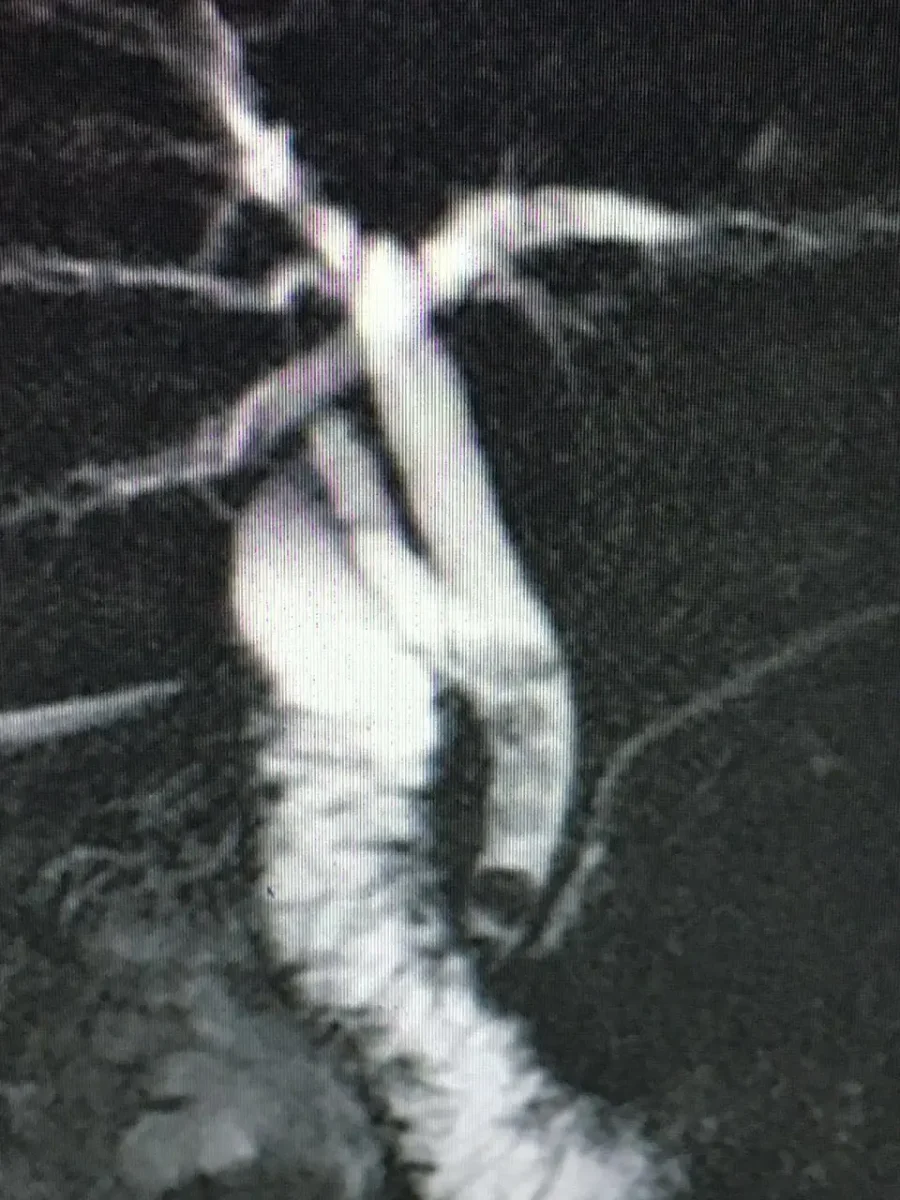

Colangioresonancia: este estudio permite evaluar la presencia de Cálculos en las vías biliares, esta condición corresponde a una enfermedad más compleja y requiere el drenaje de cálculos de la vía biliar adicionalmente a la Colecistectomía.